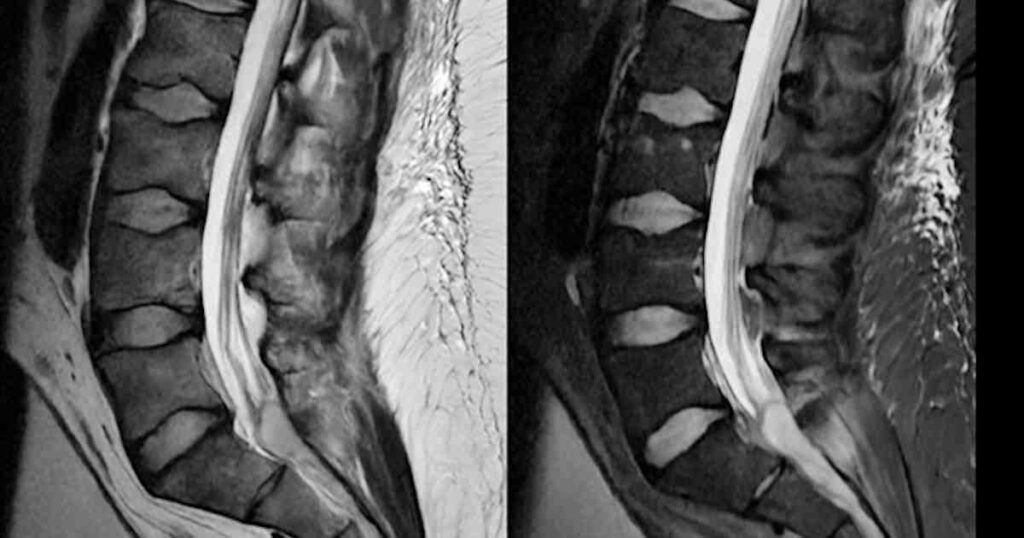

38-year-old man with back pain, radiculopathy, and fever

A 38-year-old man presented with back pain, radiculopathy, and fever.